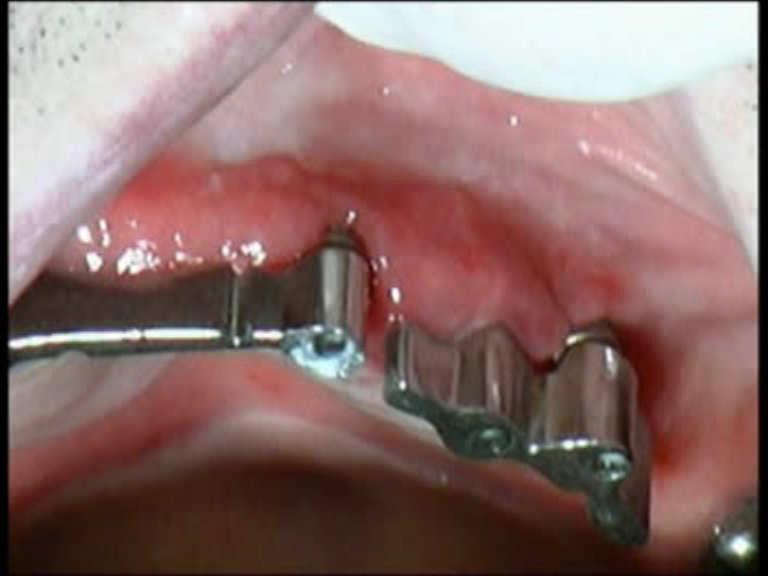

Peri-implantitis

Peri-implantitis is a dental term used to describe the destructive inflammatory process affecting the soft and hard tissues surrounding dental implants. The array of periodontal pathogens found around failing implants (those affected by peri-implantitis) are very similar to those found in association with various forms of periodontal disease.

Diode Laser 810nm

Power: 2.5 Watt,

pulsed 50 Hz

Time On/Off 10ms

Fibre 400 micron